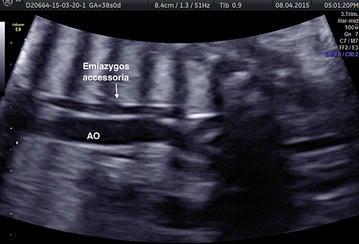

This case report describes a rare variant of azygos vein system identified in prenatal diagnosis and confirmed by postnatal ultrasonography.

本病例报告描述了一种在产前诊断中发现并经产后超声检查证实的奇静脉系统罕见变异。